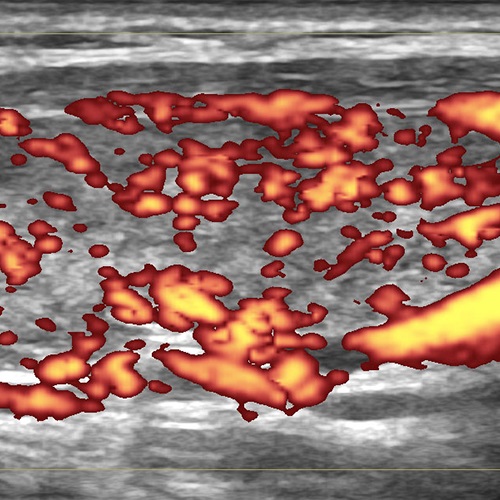

Допплеровское ультразвуковое исследование

Допплерография щитовидной железы является важным способом изучения её ФУНКЦИОНАЛЬНОГО состояния, а именно ― величины напряжения частей щитовидной железы.

Изучение состояния и изменений только в серой шкале (В-режим) выявляет структурные особенности (т.е. анатомическое и гистологическое устройство) состояния щитовидной железы. Но допплеровское исследование значительно дополняет диагностику, сообщая о функциональном состоянии измененных участков в железе и всего органа в целом... Далее →